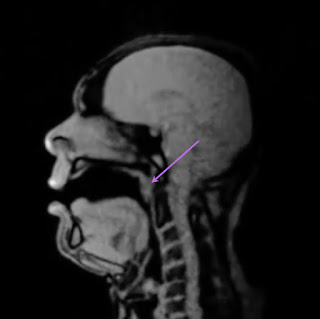

However, when eating and talking, the soft palate will lift up and close off this passage between the soft palate and back wall. You can see this in Image 2. The purple arrow points to where the soft palate has closed up against the back wall preventing any air (or food/liquids) from getting up into the nose.

![]() |

| Image 2: Normal closed position. |